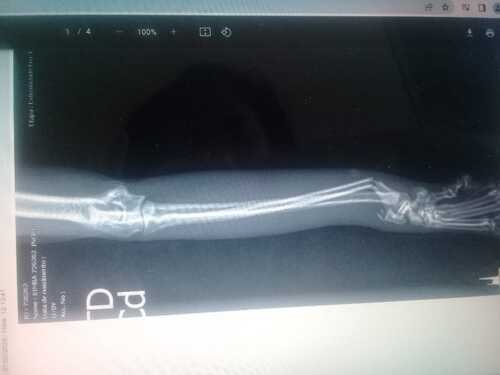

Na queda a Simba abriu o céu da boca, quebrou o fêmur esquerdo e a pata direita. No mesmo dia fomos ao veterinário público que fica localizado na Casa verde Alta na Z/N, ficamos 3 dias indo para o hospital tomar medicações e fazendo exames.

O hospital público oferece a cirurgia apenas do fêmur, não disseram motivo, mas eles não fazem o da pata da frente, fui orientada realizar primeiro a cirurgia da pata que é mais urgente, pois se o osso colar torto, ela terá problemas futuros nas articulações.

Temos o prazo de 30 dias para realizar a cirurgia da pata e retornar ao público para fazer a cirurgia do fêmur.